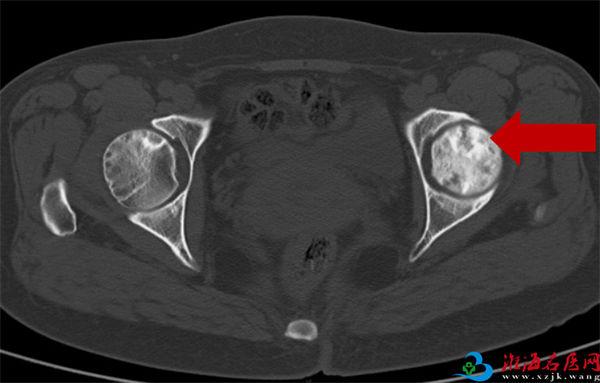

2020年8月6日CT:左股骨头囊样坏死区

2008年10月21日CT显示:

右股骨头坏死二期

2021年05月20日末次复查CT显示:

右股骨头坏死三期,左股骨头正常